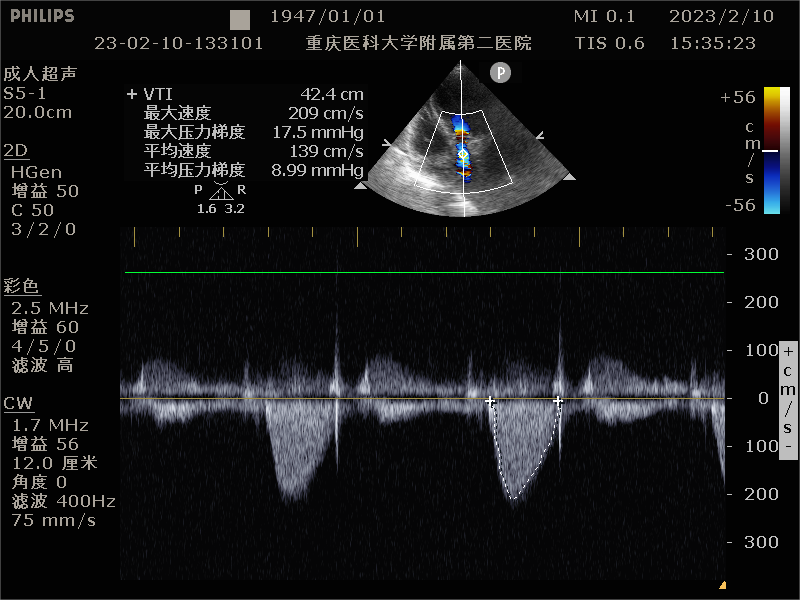

患者为76岁女性,因“反复喘累半月”入院。心脏彩超显示,左房、左室增大,升主动脉增宽,肺动脉增宽。收缩期主动脉瓣口流速350cm/s,平均压差:27mmHg,最大压差49mmHg,舒张期主动脉瓣口左室侧见大量红色为主的花色血流信号,速度438cm/s;EF 48%。诊断主动脉瓣中度狭窄伴重度关闭不全、左房、左室增大、心包积液(少量)、左室收缩功能降低、二尖瓣重度关闭不全、三尖瓣轻度关闭不全。既往患有高血压。

术后超声提示无反流

术后压力